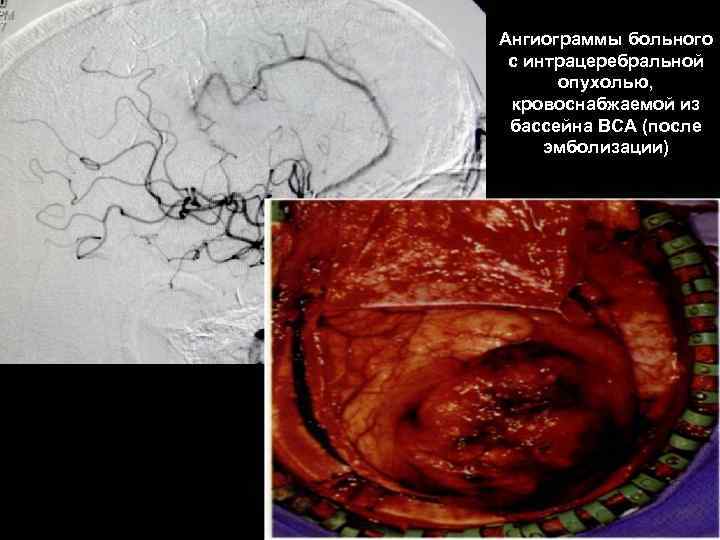

Ангиограммы больного с интрацеребральной опухолью, кровоснабжаемой из бассейна ВСА (после эмболизации) 61